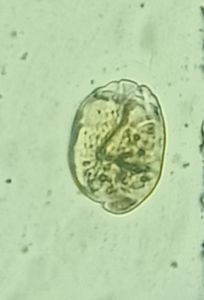

I am Dr.S.Meignanalakshmi, working as Professor, at the Directorate of Centre for Animal Health Studies, TANUVAS, Chennai-51. Working on Foldscope project on "Foldscope for diagnosis of Rumen Acidosis and parasitic infections in cattle" sanctioned by DBT